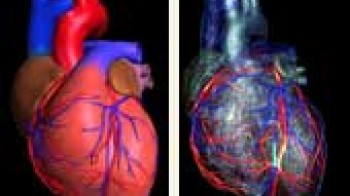

Kardiovaskularne bolesti su ubica broj jedan u današnjem svijetu i odnose svake godine više života nego sve maligne bolesti zajedno. Koronarna bolest je najčešće uzrokovana aterosklerozom (stvaranjem plakova u zidu krvnih žila uzrokojući njihvo suženje). Donedavno, nije postojao neinvazivni način da se direktno analiziraju koronarne arterije na prisustvo aterosklerotskih promjena. Razvoj tehnologije višeslojnog CT-a (MSCT/MDCT) omogućio je detaljno trodimenzionalno prikazivanje kucajućeg srca u toku jednog zadržavanja daha. U našem dijagnostičkom centru nudimo ovu tehniku pregleda koronarnih arterija, na multi-slice aparatu, s najmodernijim softverom i minimalnom dozom zračenja.